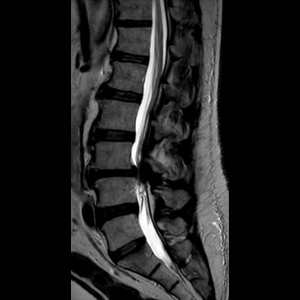

Spinal stenosis (Lumbar) Spinal stenosis (Cervical) Spinal stenosis (Thoracic) Lumbar Disc Herniation Spondylolisthesis Cervical Foraminal Stenosis Vertebroplasty Lumbar Fusion Anterior Cervical Fusion (ACDF) Posterior Cervical Fusion Thoracic Fusion Revision Lumbar Fusion Surgery Facet Joint Cyst Spinal Tumour Minimally Invasive Lumbar Fusion (XLIF) Minimally Invasive Lumbar Fusion (ALIF) Lumbar Fusion (TLIF) Thoraco-lumbar Fusion Lumbar Corpectomy Complex Lumbar Spine Surgery (Spino-pelvic fixation) Complex Cervical Spine Surgery Complex Thoracic Spine Surgery Occipito-cervical Fusion Minimally invasive surgery for thoracic disc herniation Other Related Topics